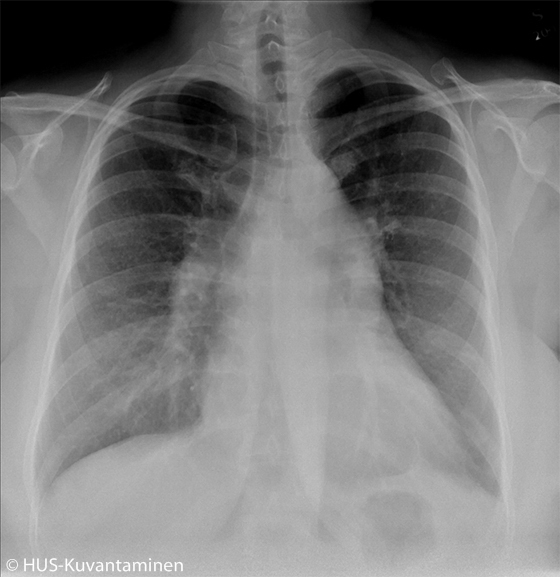

Kohonnut keuhkoverenpaine (kuva ilman löydösmerkintöjä).

Nuorella naisella oli hengenahdistusta ja huonovointisuutta.

Kuva: HUS-Kuvantaminen